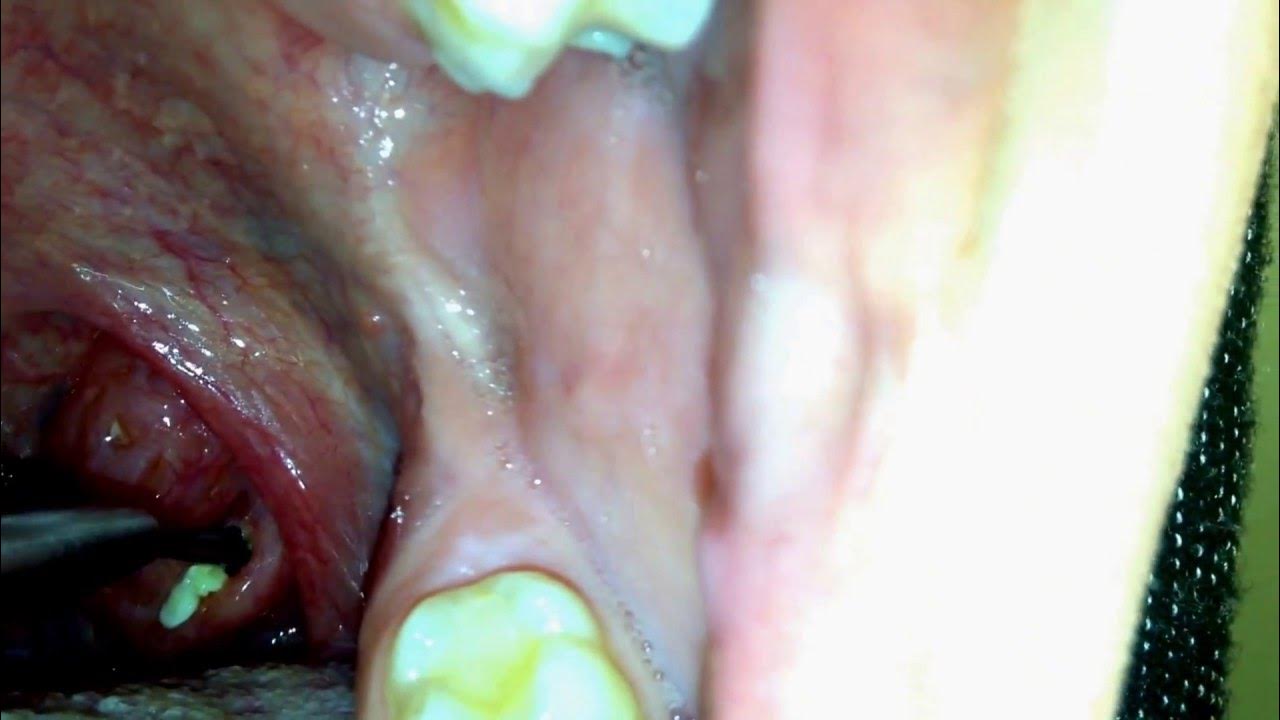

Removing Tonsil Stones! Removing Big Tonsil Stones! YouTube

Giant Tonsil Stones! Dr. G's Biggest Tonsil Stone Ever! YouTube Big World Record Tonsil Stones The largest tonsils are those of patrick kelleher (usa), the left of which measured 6.0 cm (2.4 in) long, 3.5 cm (1.4 in) wide and 3.0 cm (1.2 in). Have you ever wondered what the largest tonsil stone ever recorded is? Tonsil stones, also known as tonsilloliths, are small, hard calcifications that form in the. The patient underwent elective stone. Big World Record Tonsil Stones.

Multitude of Massive Tonsil stones removed! AIM 20 YouTube Big World Record Tonsil Stones Tonsil stones, also known as tonsilloliths, are small, hard calcifications that form in the. At moore's institute.tens of millions of people. Have you ever wondered what the largest tonsil stone ever recorded is? Removal/extraction done in denver colorado. The patient underwent elective stone removal and. 30k subscribers in the tonsilstones community. The largest tonsils are those of patrick kelleher (usa),. Big World Record Tonsil Stones.